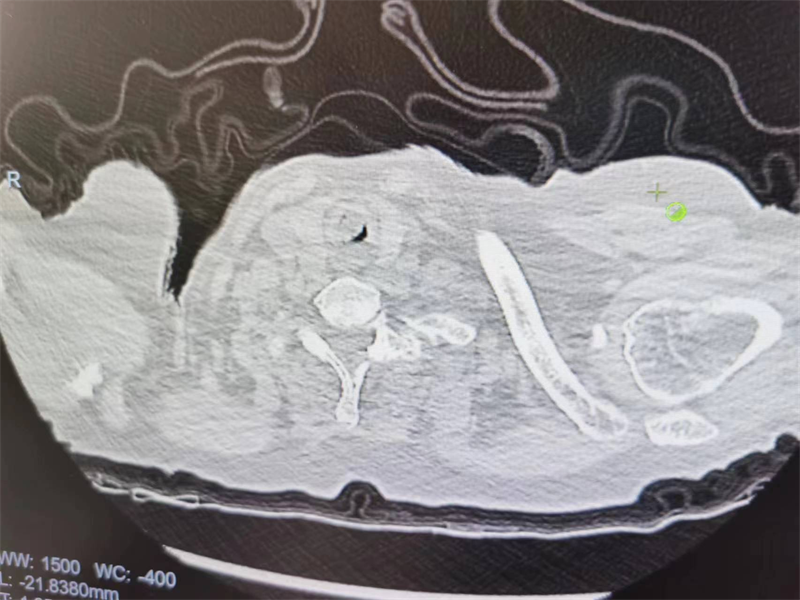

患者2,侯某,因发现食管癌3年余,咳嗽、呼吸困难20天,急诊收住我院呼吸监护室,患者入院时呼吸急促、紫绀、氧饱和度降至最低50-60%,给与呼吸机辅助呼吸后稍有缓解,胸部CT提示患者食管肿瘤已侵犯气管,气管重度狭窄(约90%),随时有窒息风险。

呼吸介入团队经充分评估后,决定急诊行气管镜下介入手术,在全身麻醉下,顺利的插入硬质支气管镜,通过软硬镜结合对气管内的肿瘤进行铲切、高频电刀烧灼、冻取等多种介入技术,很快切除大部分肿瘤,同时置入金属支架一枚,支架扩张良好,术后患者呼吸困难很快得到缓解,并拔除气管插管,转至普通病房。